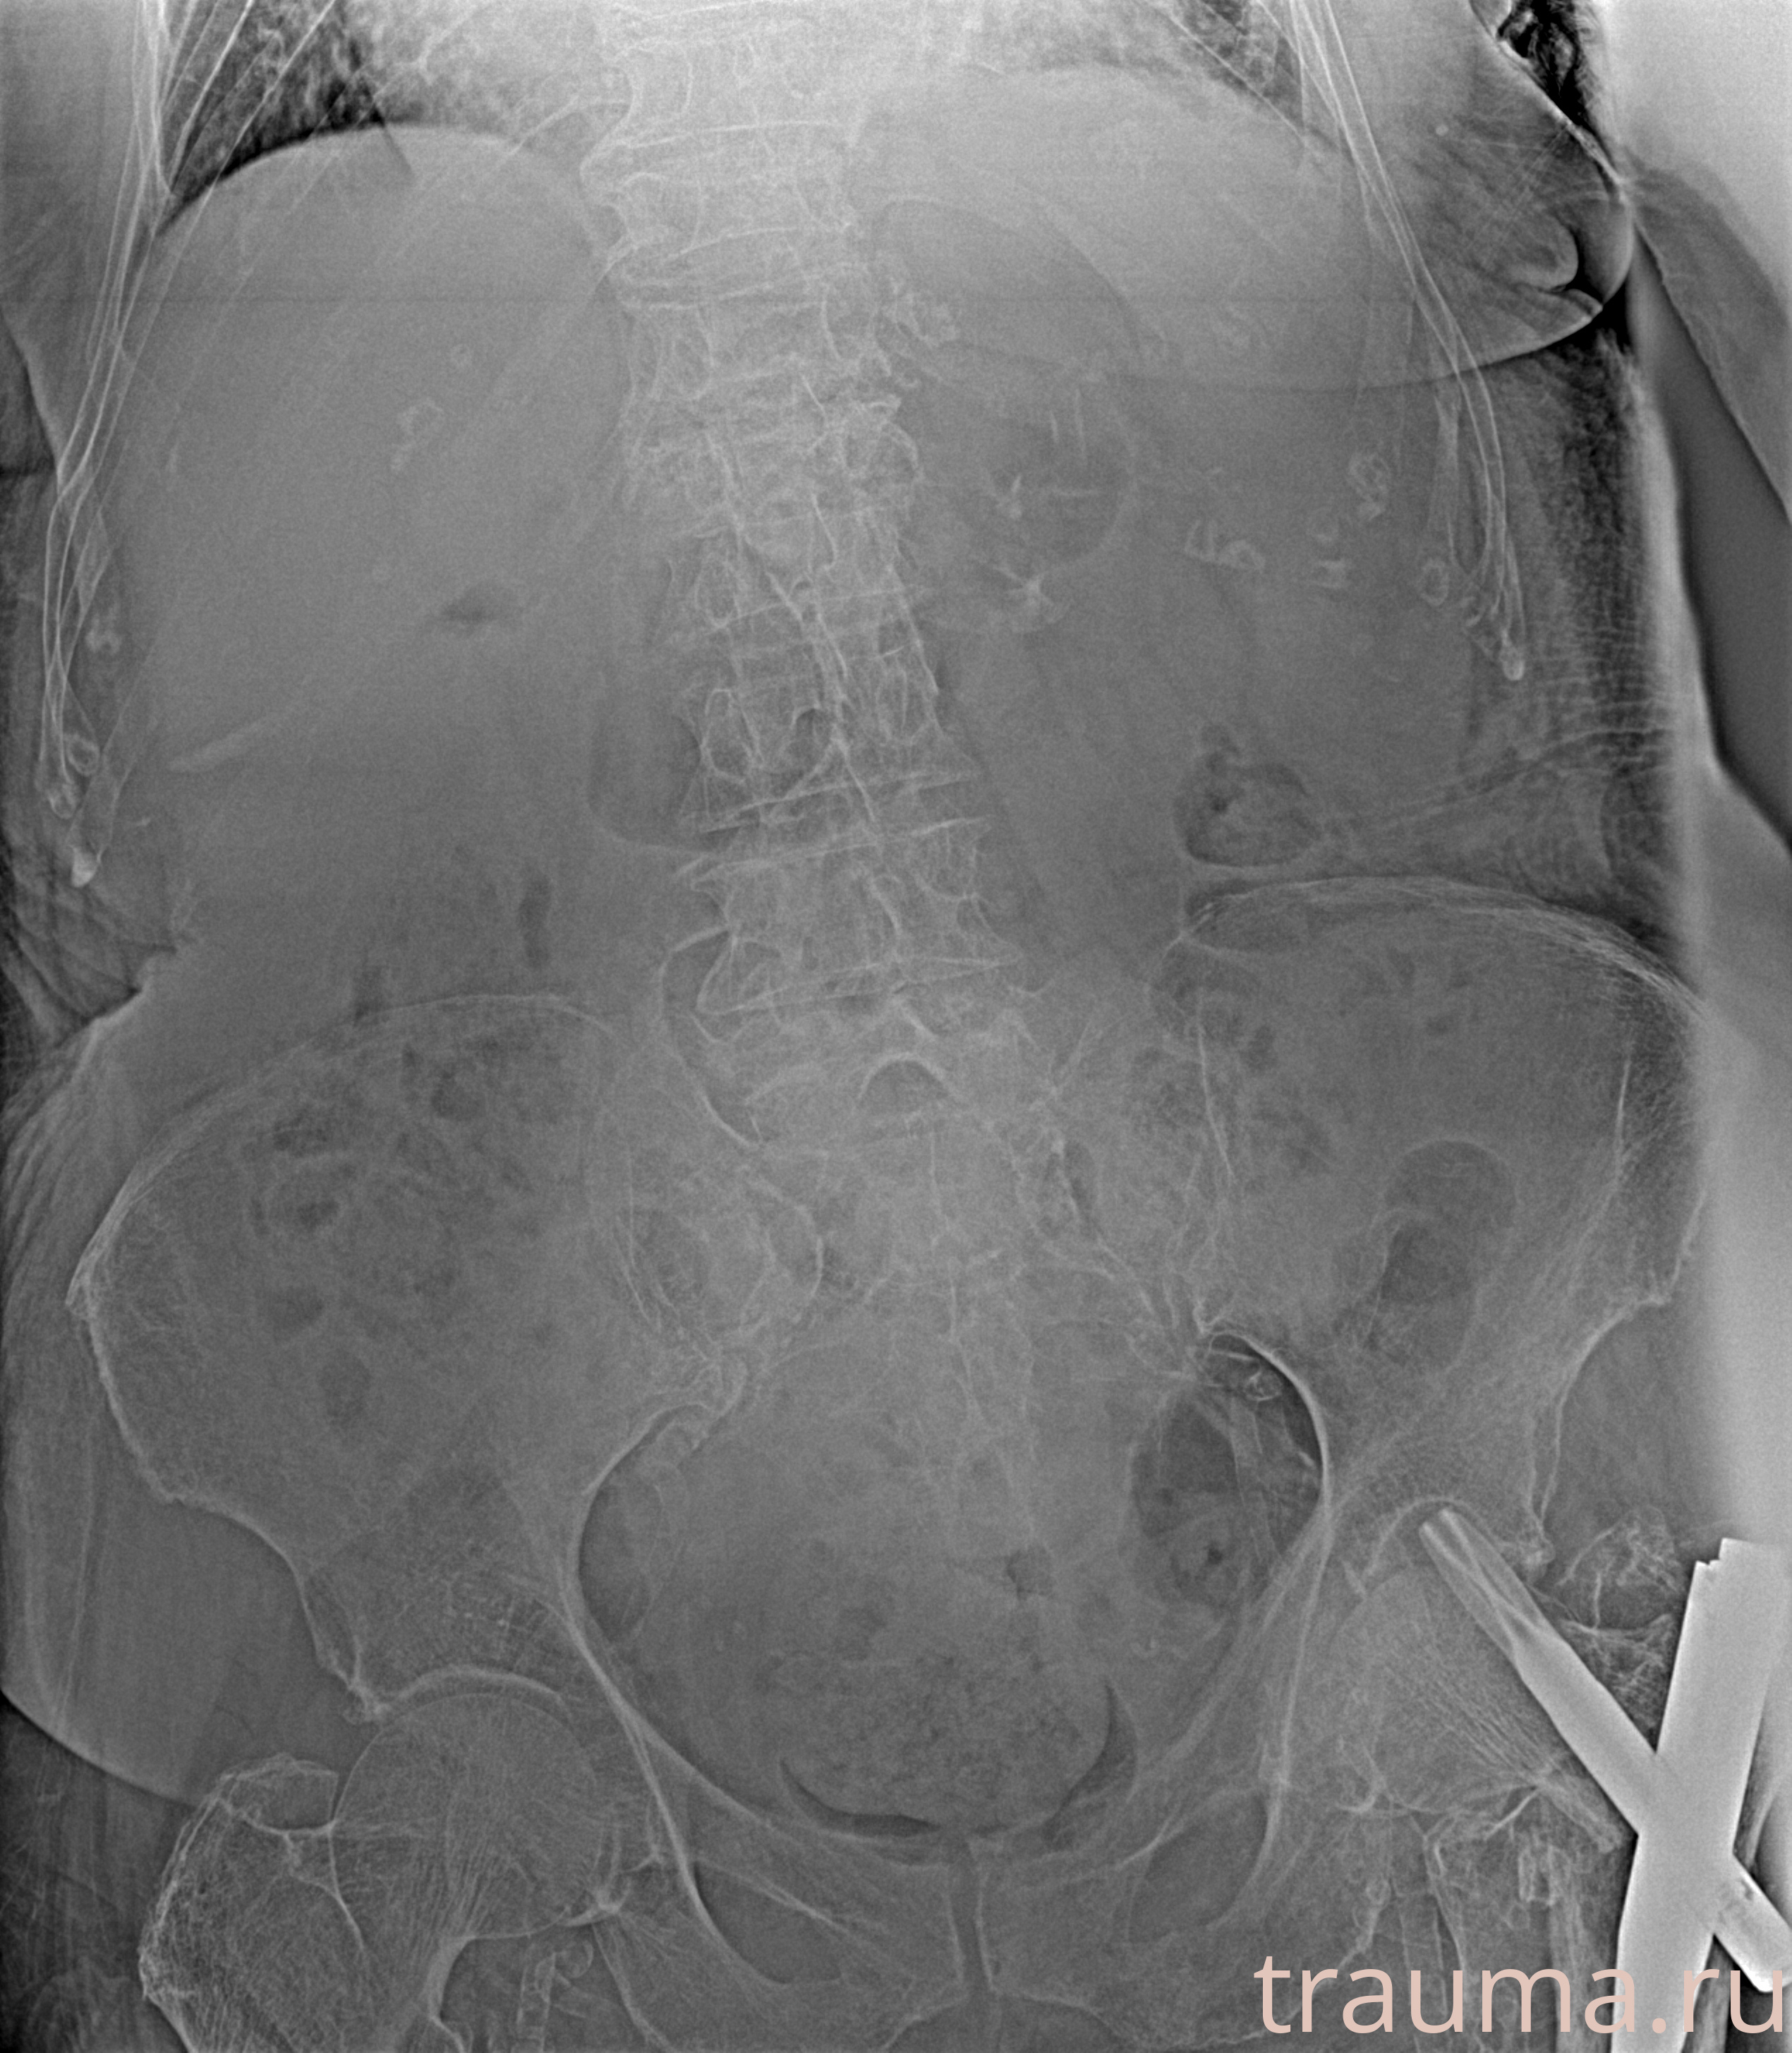

Рентгенограммы

Рентген на дому: по вашему адресу приезжает врач-рентгенолог, травматолог-ортопед с мобильным рентгеновским аппаратом, проводит диагностику травмы или заболевания, делает необходимые рентгенограммы, дает рекомендации по дальнейшему лечению. Получить качественные снимки в домашних условиях возможно благодаря уникальной методике, разработанной МосРентген Центром для института  Склифосовского